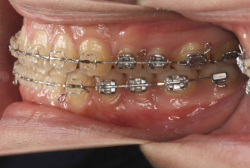

歯科矯正用アンカースクリューを用いた症例(骨格性反対咬合 非抜歯治療)

「ものがうまく噛めない」という主訴で来院したケースです。診断の結果、「骨格性反対咬合に伴う咬合不良+軽度叢生」と判明しました。原因としては特に下顎の左側が過成長したため、骨格性反対咬合になり、特に左側での噛み合わせが非常に悪くなっていると診断しました。初診時の写真を見ると、上下の正中線の大きなズレ、左側の噛み合わせの不良がはっきり分かります(黄色の矢印と緑の矢印は一致しているのが正しい状態です)。

そもそも、このような状態となっているのは骨の大きさに問題があるため生じていますので、場合によっては、「外科矯正」によって下顎の骨を外科的に縮めることで修正します。患者様が外科矯正をご希望されない場合は、従来ですと上下左右の小臼歯抜歯を行い矯正するのが普通です。

今回の患者様の場合は、「外科」も「小臼歯抜歯」も拒否されましたので、歯科矯正用アンカースクリュー(以下 アンカースクリュー)を用いて、下顎の歯列全体を後方に下げるという方法を取りました。

治療中の写真で、アンカースクリューより歯を後ろへ牽引しているのがお分かりいただけるかと思います。牽引を1年ほど続け、途中補助的に上下にゴムをかける(これを顎間ゴムと言います)手法なども追加し、全体で21ヶ月で治療を終えることが出来ました。

結局歯の本数を減らすことなく、すべてご自分の歯を残して、正しい配列と噛み合わせにすることができました。凸凹があまりひどくないため、簡単そうに見えると思いますが、このケースの初診の状態を見ると、熟練の矯正歯科医でも悩みのつきないケースです。まして、外科も出来ない、抜歯もイヤ、と言うことになると、従来の方法では治療不可能と考えられるのですが、アンカースクリューを使うことで最近は不可能が可能となってきました。